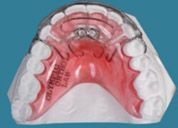

Other types of orthodontic appliances may also be used during the course of treatment. Some of these appliances are removable and can be taken in and out of the mouth, while others will be attached to the teeth until they are no longer needed.

Depending upon the specific needs of the case, these appliances may be used to accomplish a number of things including:

- Widening the jaws to make sufficient space for permanent teeth

- Influencing jaw growth

- The reduction of deep overbites

- Allowing the correction of teeth in crossbite

- Maintaining the space for a permanent tooth when a baby tooth has been prematurely lost

- Minor tooth movement

- Helping to control harmful oral habits